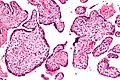

| Micrograph of villitis of unknown etiology. H&E stain. | |

Histomorphologically, VUE is characterized by a lymphocytic infiltrate of the chorionic villi without a demonstrable cause. Plasma cells should be absent; the presence of plasma cells suggests an infective etiology, e.g. CMV infection.